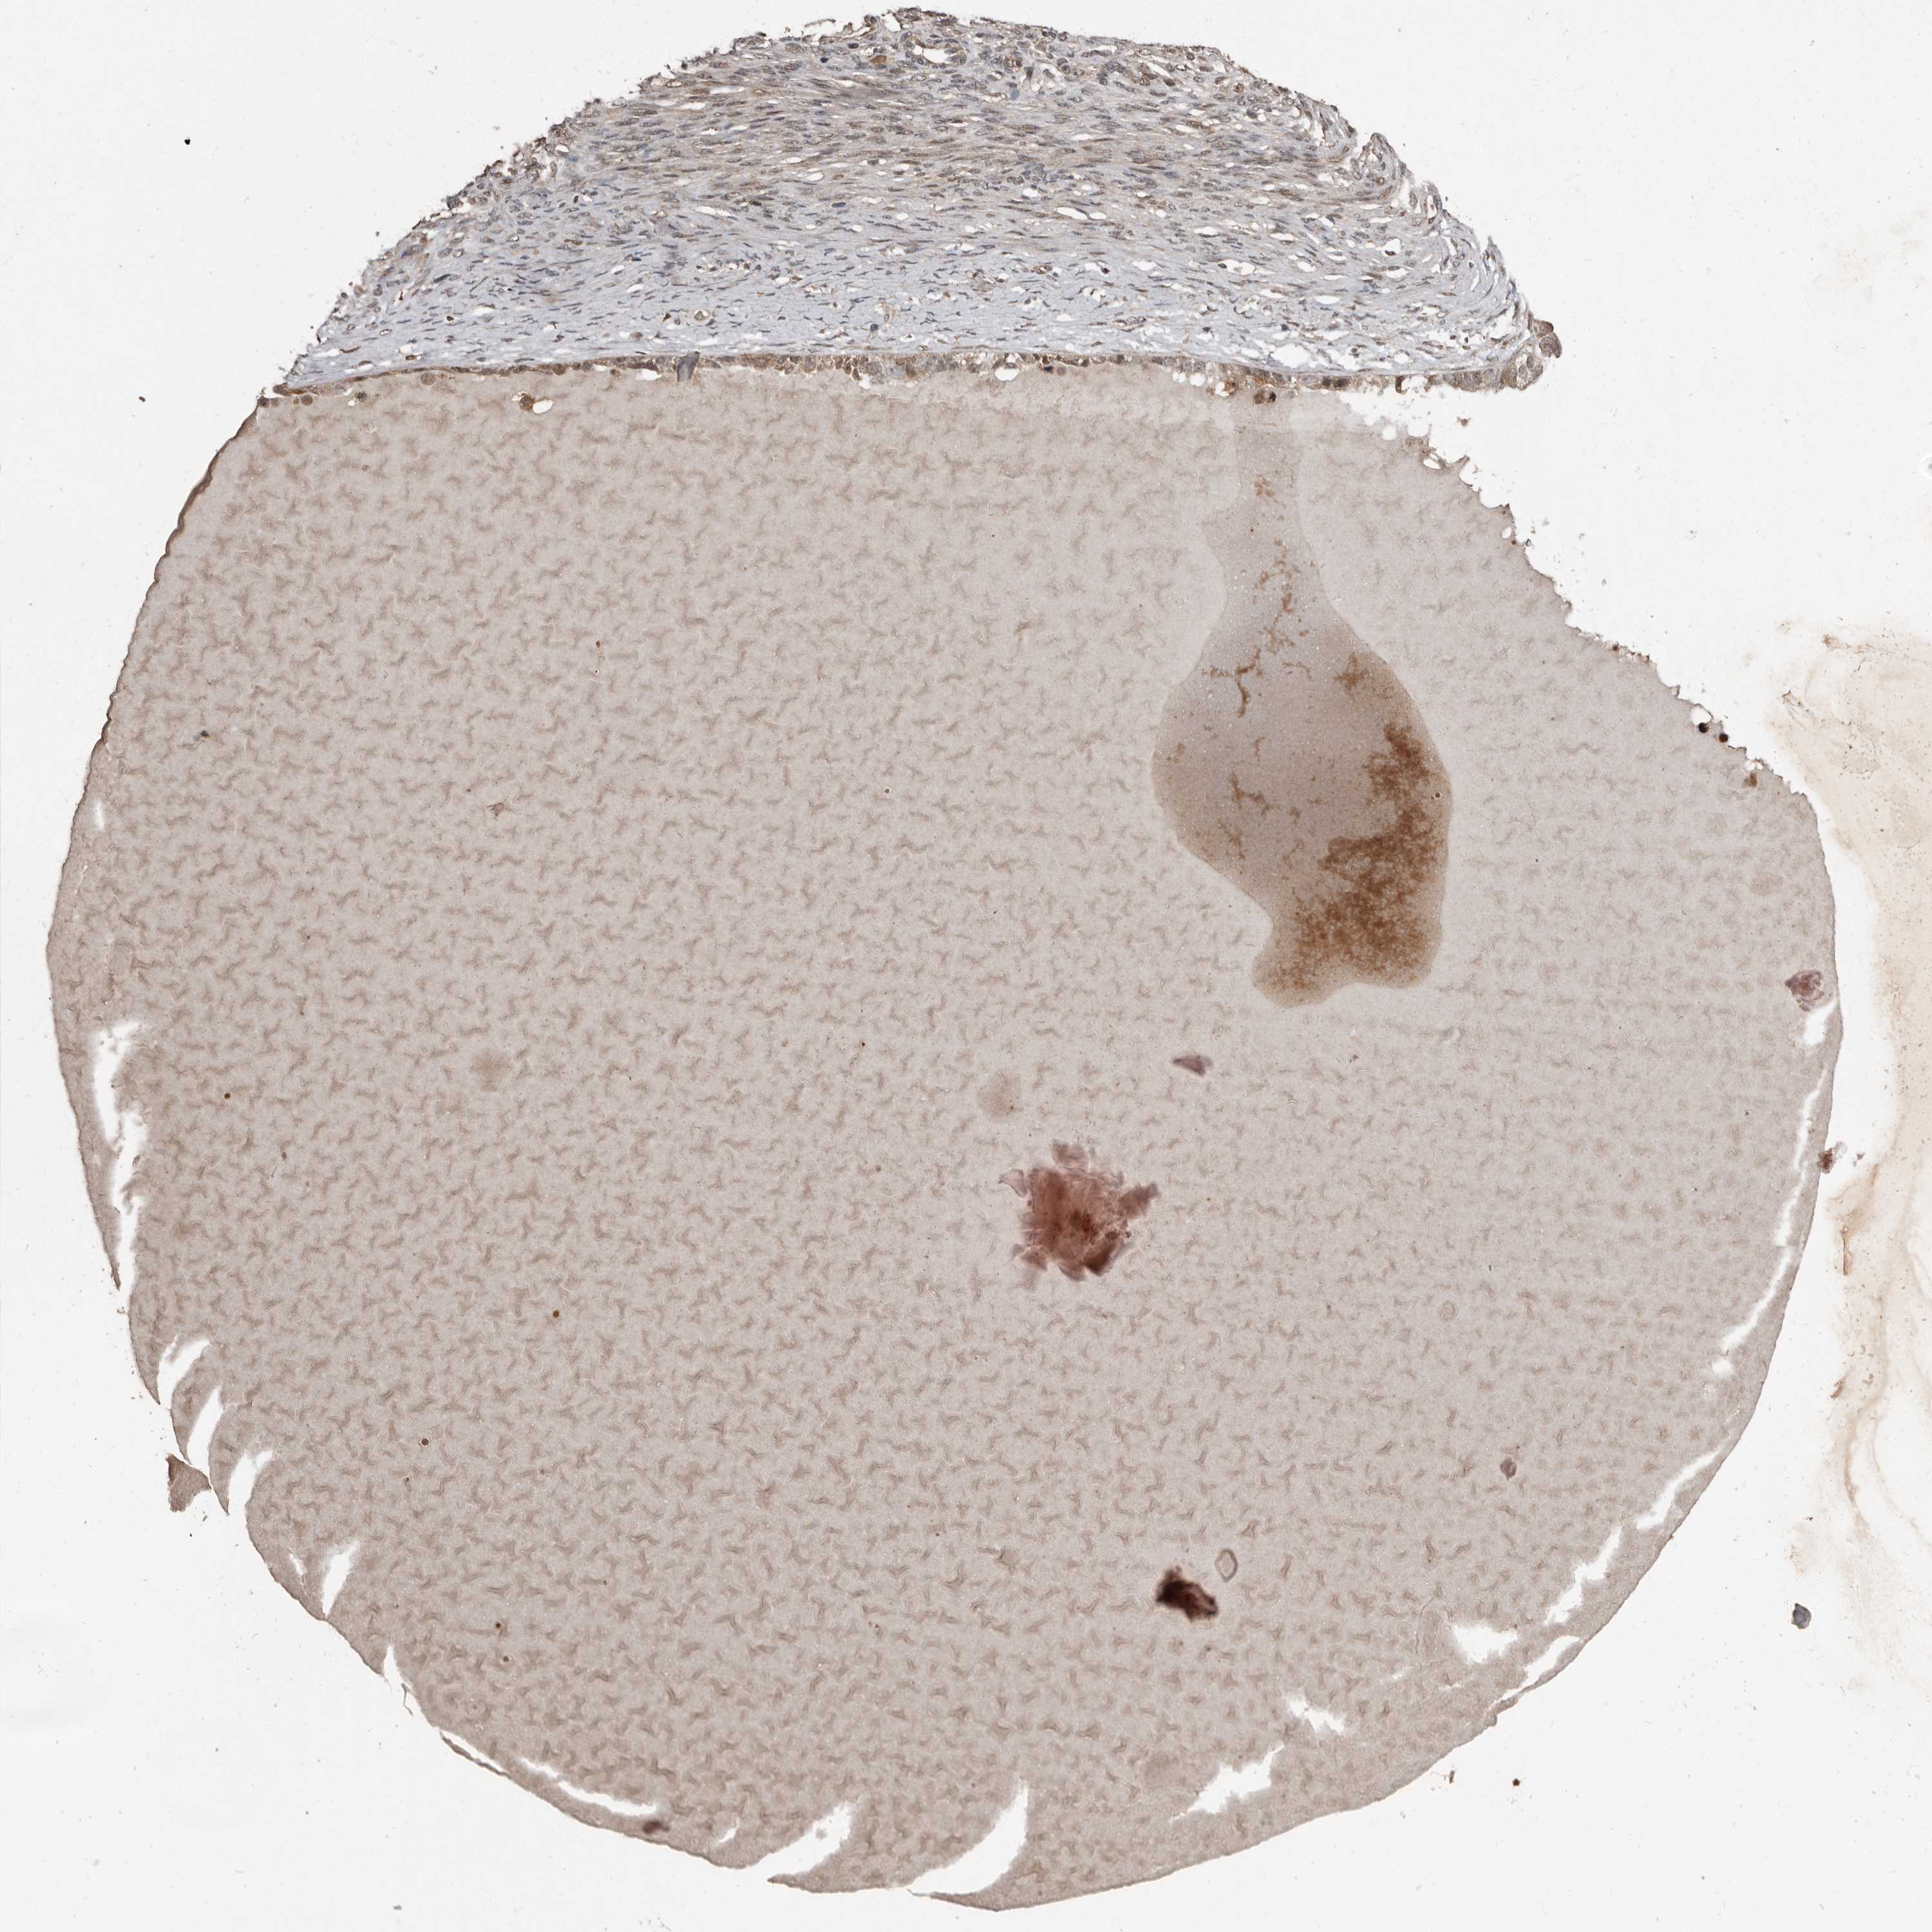

OVARIAN CANCER - Protein expressioni

A mouse-over function shows sample information and annotation data. Click on an image to view it in a full screen mode. Samples can be filtered based on level of antibody staining by selecting one or several of the following categories: high, medium, low and not detected. The assay and annotation is described here.

Note that samples used for immunohistochemistry by the Human Protein Atlas do not correspond to samples in the TCGA dataset.

Antibody stainingi

Antibody staining in the annotated cell types in the current human tissue is reported as not detected, low, medium, or high, based on conventional immunohistochemistry profiling in selected tissues. This score is based on the combination of the staining intensity and fraction of stained cells.

Each image is clickable and will lead to virtual microscopy that enables deeper exploration of all samples and also displays staining intensity scores, fraction scores and subcellular localization as well as patient and tissue information for each sample.

Antibody HPA026509

Staining

High

Medium

Low

Not detected

Intensity

Strong

Moderate

Weak

Negative

Quantity

>75%

75%-25%

<25%

None

Location

Nuclear

Cytoplasmic/membranous

Cytoplasmic/membranous,nuclear

Cystadenocarcinoma, serous, NOS

Carcinoma, endometroid

Cystadenocarcinoma, mucinous, NOS

Carcinoma, NOS